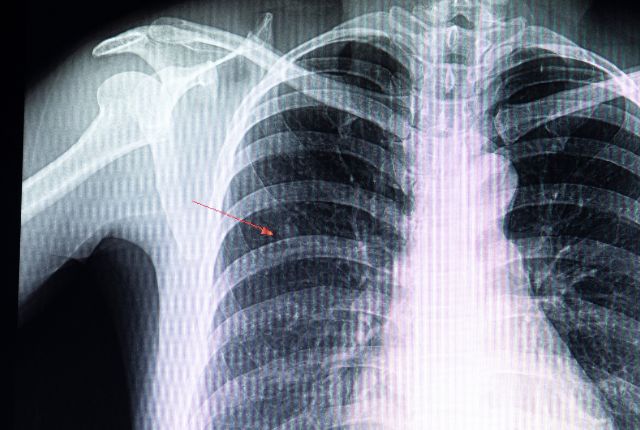

Certains nodules correspondent à des tumeurs non agressives et sans danger. Toutefois, la présence de nodules peut également révéler un cancer du poumon. Parfois, ils témoignent de la propagation d’un cancer provenant d’un autre organe, comme le sein ou le côlon, sous forme de métastases. C’est pourquoi les médecins s’attachent à identifier précisément la nature du nodule détecté, notamment à l’aide d’une radiographie ou, de manière plus fiable, grâce à un scanner.

Un nodule est une masse souvent solide de forme arrondie, constituée de cellules et/ou de tissus. Lorsqu’il se situe sous la peau, il peut parfois être perçu au toucher. Cependant, s’il est localisé plus en profondeur, comme dans les poumons, il reste indétectable par palpation. Selon sa taille, il peut être mis en évidence lors d’un examen d’imagerie médicale, tel qu’une radiographie ou un scanner, et souvent découvert de manière fortuite. Bien que la majorité des nodules soient bénins et constituent une anomalie fréquente chez l’être humain, certains peuvent révéler la présence d’une tumeur maligne.